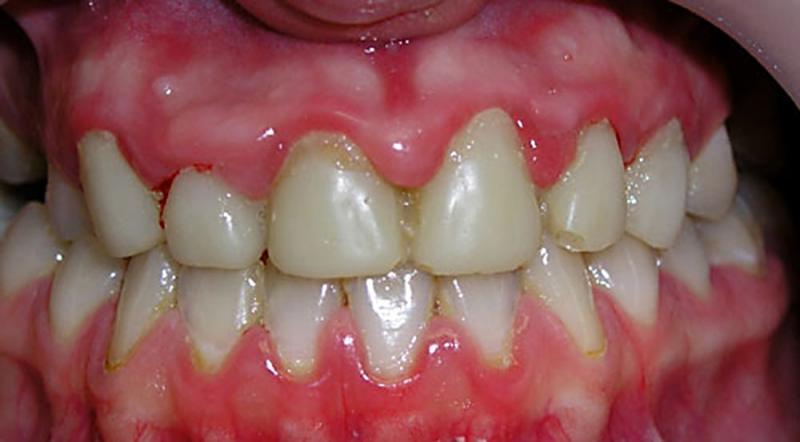

Хронический катаральный гингивит (см. фото) представляет собой следующую стадию заболевания. Симптомы становятся менее выраженными и чаще всего проявляются в моменты снижения иммунитета, во время еды и чистки зубов.

Основные симптомы включают:

- болезненные ощущения при приёме пищи и гигиенических процедурах;

- кровотечение из дёсен во время чистки зубов;

- постоянная гиперемия поражённых десен;

- отслаивание межзубных сосочков от зубов;

- отёк краёв десен.

Обычно симптомы хронической формы не так ярко выражены, и их можно заметить только во время визита к стоматологу.

В периоды обострения симптомы становятся схожими с острой формой, что значительно упрощает диагностику гингивита.

При осмотре полости рта врач обращает внимание на состояние десен, их цвет, текстуру и наличие отека. Для острого катарального гингивита характерно покраснение и отек десен, а также их болезненность при пальпации. Десны могут быть легко кровоточащими, особенно при чистке зубов или при легком нажатии. Важно отметить, что в отличие от других форм гингивита, при катаральном типе воспаление обычно ограничивается только деснами, без вовлечения более глубоких тканей.